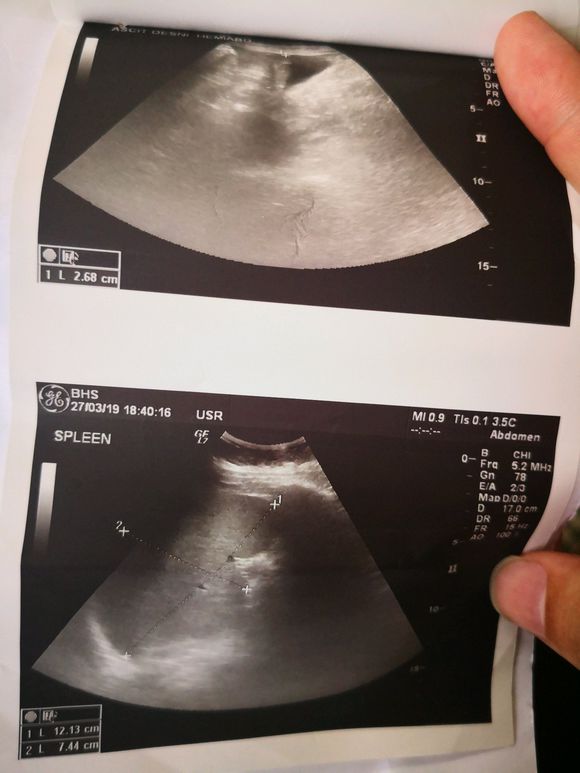

好梦成真 02019-07-29 患者家属爸爸今年本命年刚满60岁是个该享福的年龄1月初胃胀后2月26日确诊肝癌晚期没有治疗意义之后出院保守治疗一直吃靶向药有过一...

北极熊欢欢 02019-07-24 患者家属我父亲去年8月份发现肝癌说是早中期肿瘤大概3CM,但是其他肝功能都正常。我们没有做手术,做了两次介入。一直在吃靶向药,索...